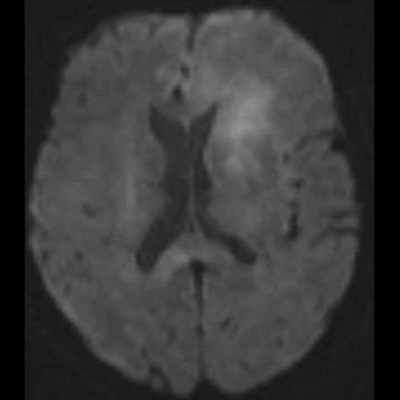

- (A) Her iki periventriküler beyaz cevherde aksiyel T2A, FLAIR serilerde hiperintens, T1A hipointens geniş ödem alanları (oklar) izlenmektedir. Sol frontalde T2A’da hipointens kitle lezyonuna (ok) dikkat ediniz.

- (C) Difüzyon ağırlıklı görüntülerde sol frontaldeki kitle lezyonunda difüzyon kısıtlama bulgusu (oklar) mevcut olup perfüzyon MRG’de rCBV haritasında belirgin perfüzyon artışı izlenmemektedir (ok).

- MRG’de, lenfomalar tipik olarak T2A sekanslarda hipointens olup DAG’de belirgin difüzyon kısıtlanması gösterirler.

- T2 sinyali belirgin düşük olgularda b=1000 görüntülerde hipointens görünüm izlenebilir ve T2 kararması (T2 black-out) etkisi olarak adlandırılan bu durum yanlış yorumlamalara yol açabilir. Bu nedenle gerçek difüzyon kısıtlamasını değerlendirmede ADC haritaları daha güvenilirdir.